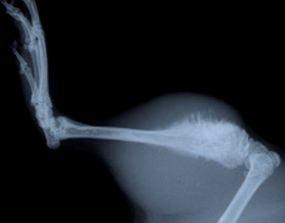

Рак костей

Рак костей — собирательное понятие. Сами по себе онкологические заболевания костей относительно редки — не более 1% всех случаев диагностированных опухолей. Но большая часть опухолей других органов метастазируют (проникают) в костную ткань. Врачи в таком случае говорят о вторичной опухоли костной ткани, и только в этом случае врач может дать ответ, откуда развилась опухоль кости.

Гангрена(некроз)

Под гангреной (некрозом) понимают конечный результат распада тканей живого организма. Распад тканей возможен под влиянием как внешних, так и внутренних причин. Но всегда, вне зависимости от причины, гангрена развивается только в тех тканях, в которых имеются предпосылки для отмирания тканей, то есть так или иначе поврежденных. Учитывая, что для развития гангрены важно ухудшение трофики (питания) тканей, становится ясным, почему некроз развивается в основном отдаленных частях телах.